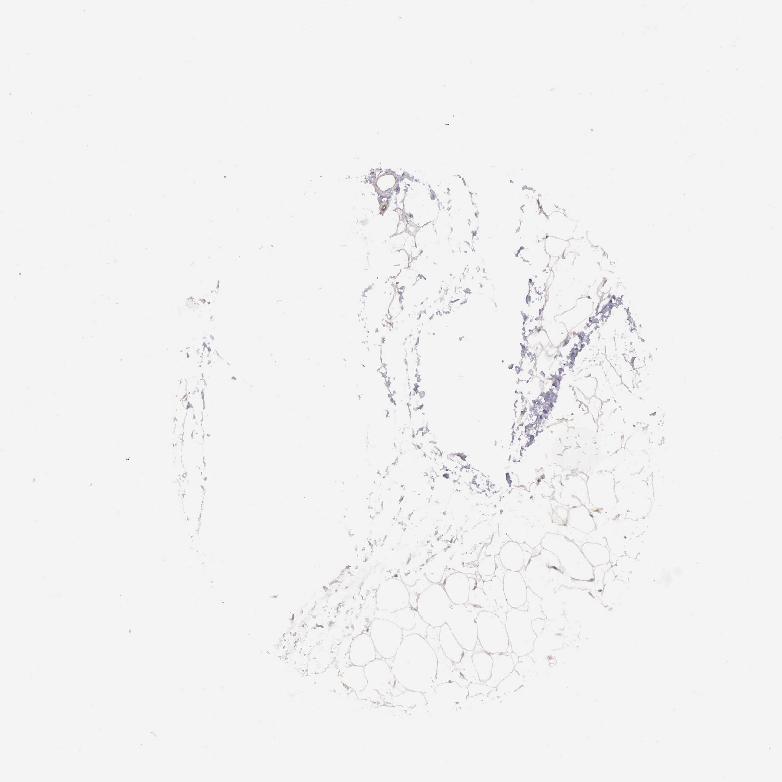

ADIPOSE TISSUE - Antibody stainingi

Antibody staining in the annotated cell types in the current human tissue is reported as not detected, low, medium, or high, based on conventional immunohistochemistry profiling in selected tissues. This score is based on the combination of the staining intensity and fraction of stained cells.

Each image is clickable and will lead to virtual microscopy that enables deeper exploration of all samples and also displays staining intensity scores, fraction scores and subcellular localization as well as patient and tissue information for each sample.

Antibody HPA001013

Adipocytes Low